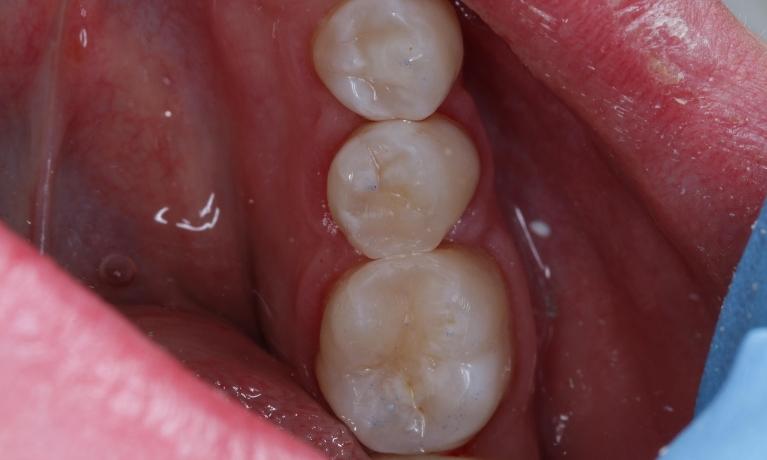

Composite fillings are usually formed using a mixture of resins, fillers, and colourants, and applied to the tooth in layers and “cured". Unlike silver amalgam fillings, composites can be made to match the colour of your natural teeth.

Since the composite bonds directly to your tooth, these fillings require less removal of healthy tooth structure, which leaves more remaining tooth structure intact. Composite fillings are also less susceptible than metal fillings to cracking and chipping due to temperature changes in your mouth.

The dentist will match the colour of your natural tooth and mix up a composite that is then applied in layers and cured between each layer. Once built up, the filling will be shaped to contour to your bite and look natural and then polished smooth.